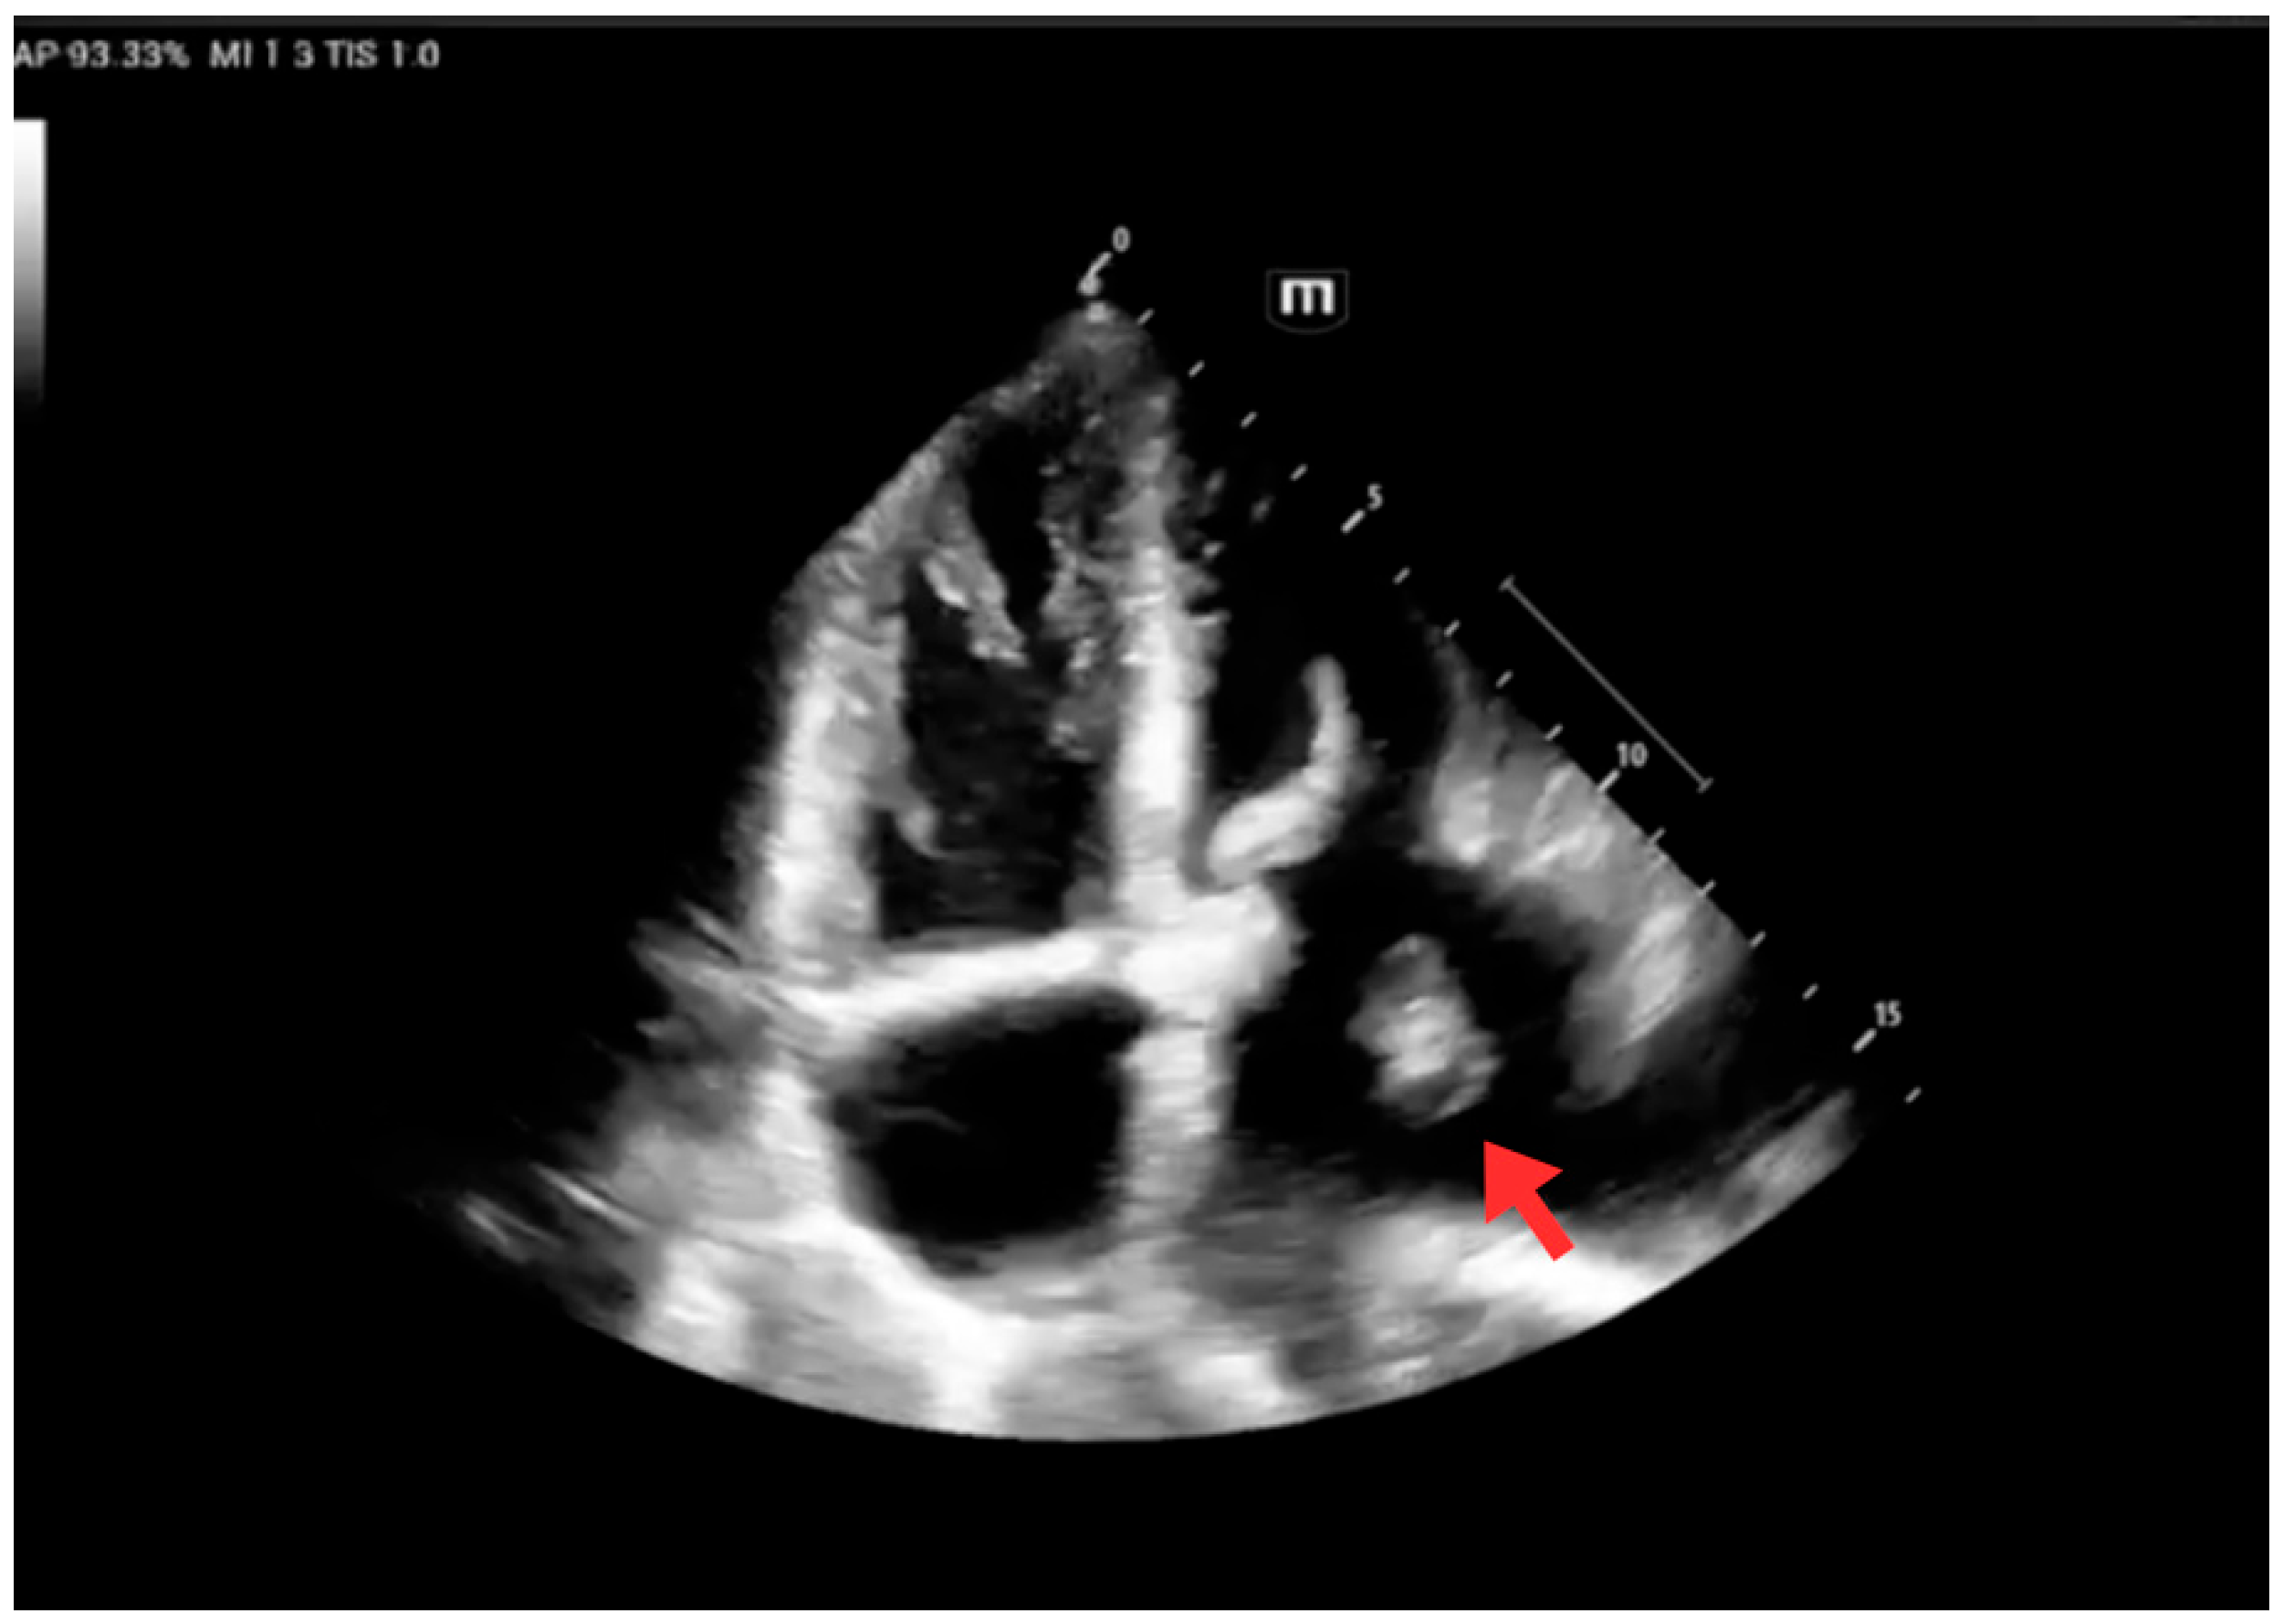

| Early inpatient workup (Day 0) | Hospital | Suspected cardioembolic source in context of arrhythmia/Chagas cardiomyopathy. | TTE: severe LA dilation + mobile LA thrombus; LVEF 45%. Labs: no major abnormalities; mild troponin I and NT-proBNP elevation. | — | Cardioembolic mechanism supported |

| Follow-up echocardiography | Hospital | Persistent LA thrombus, stable/partially organized; no fragmentation signs. | TTE: persistent thrombus; LVEF 48%. | Continue anticoagulation + rhythm control | Thrombus stable; preserved LV function |